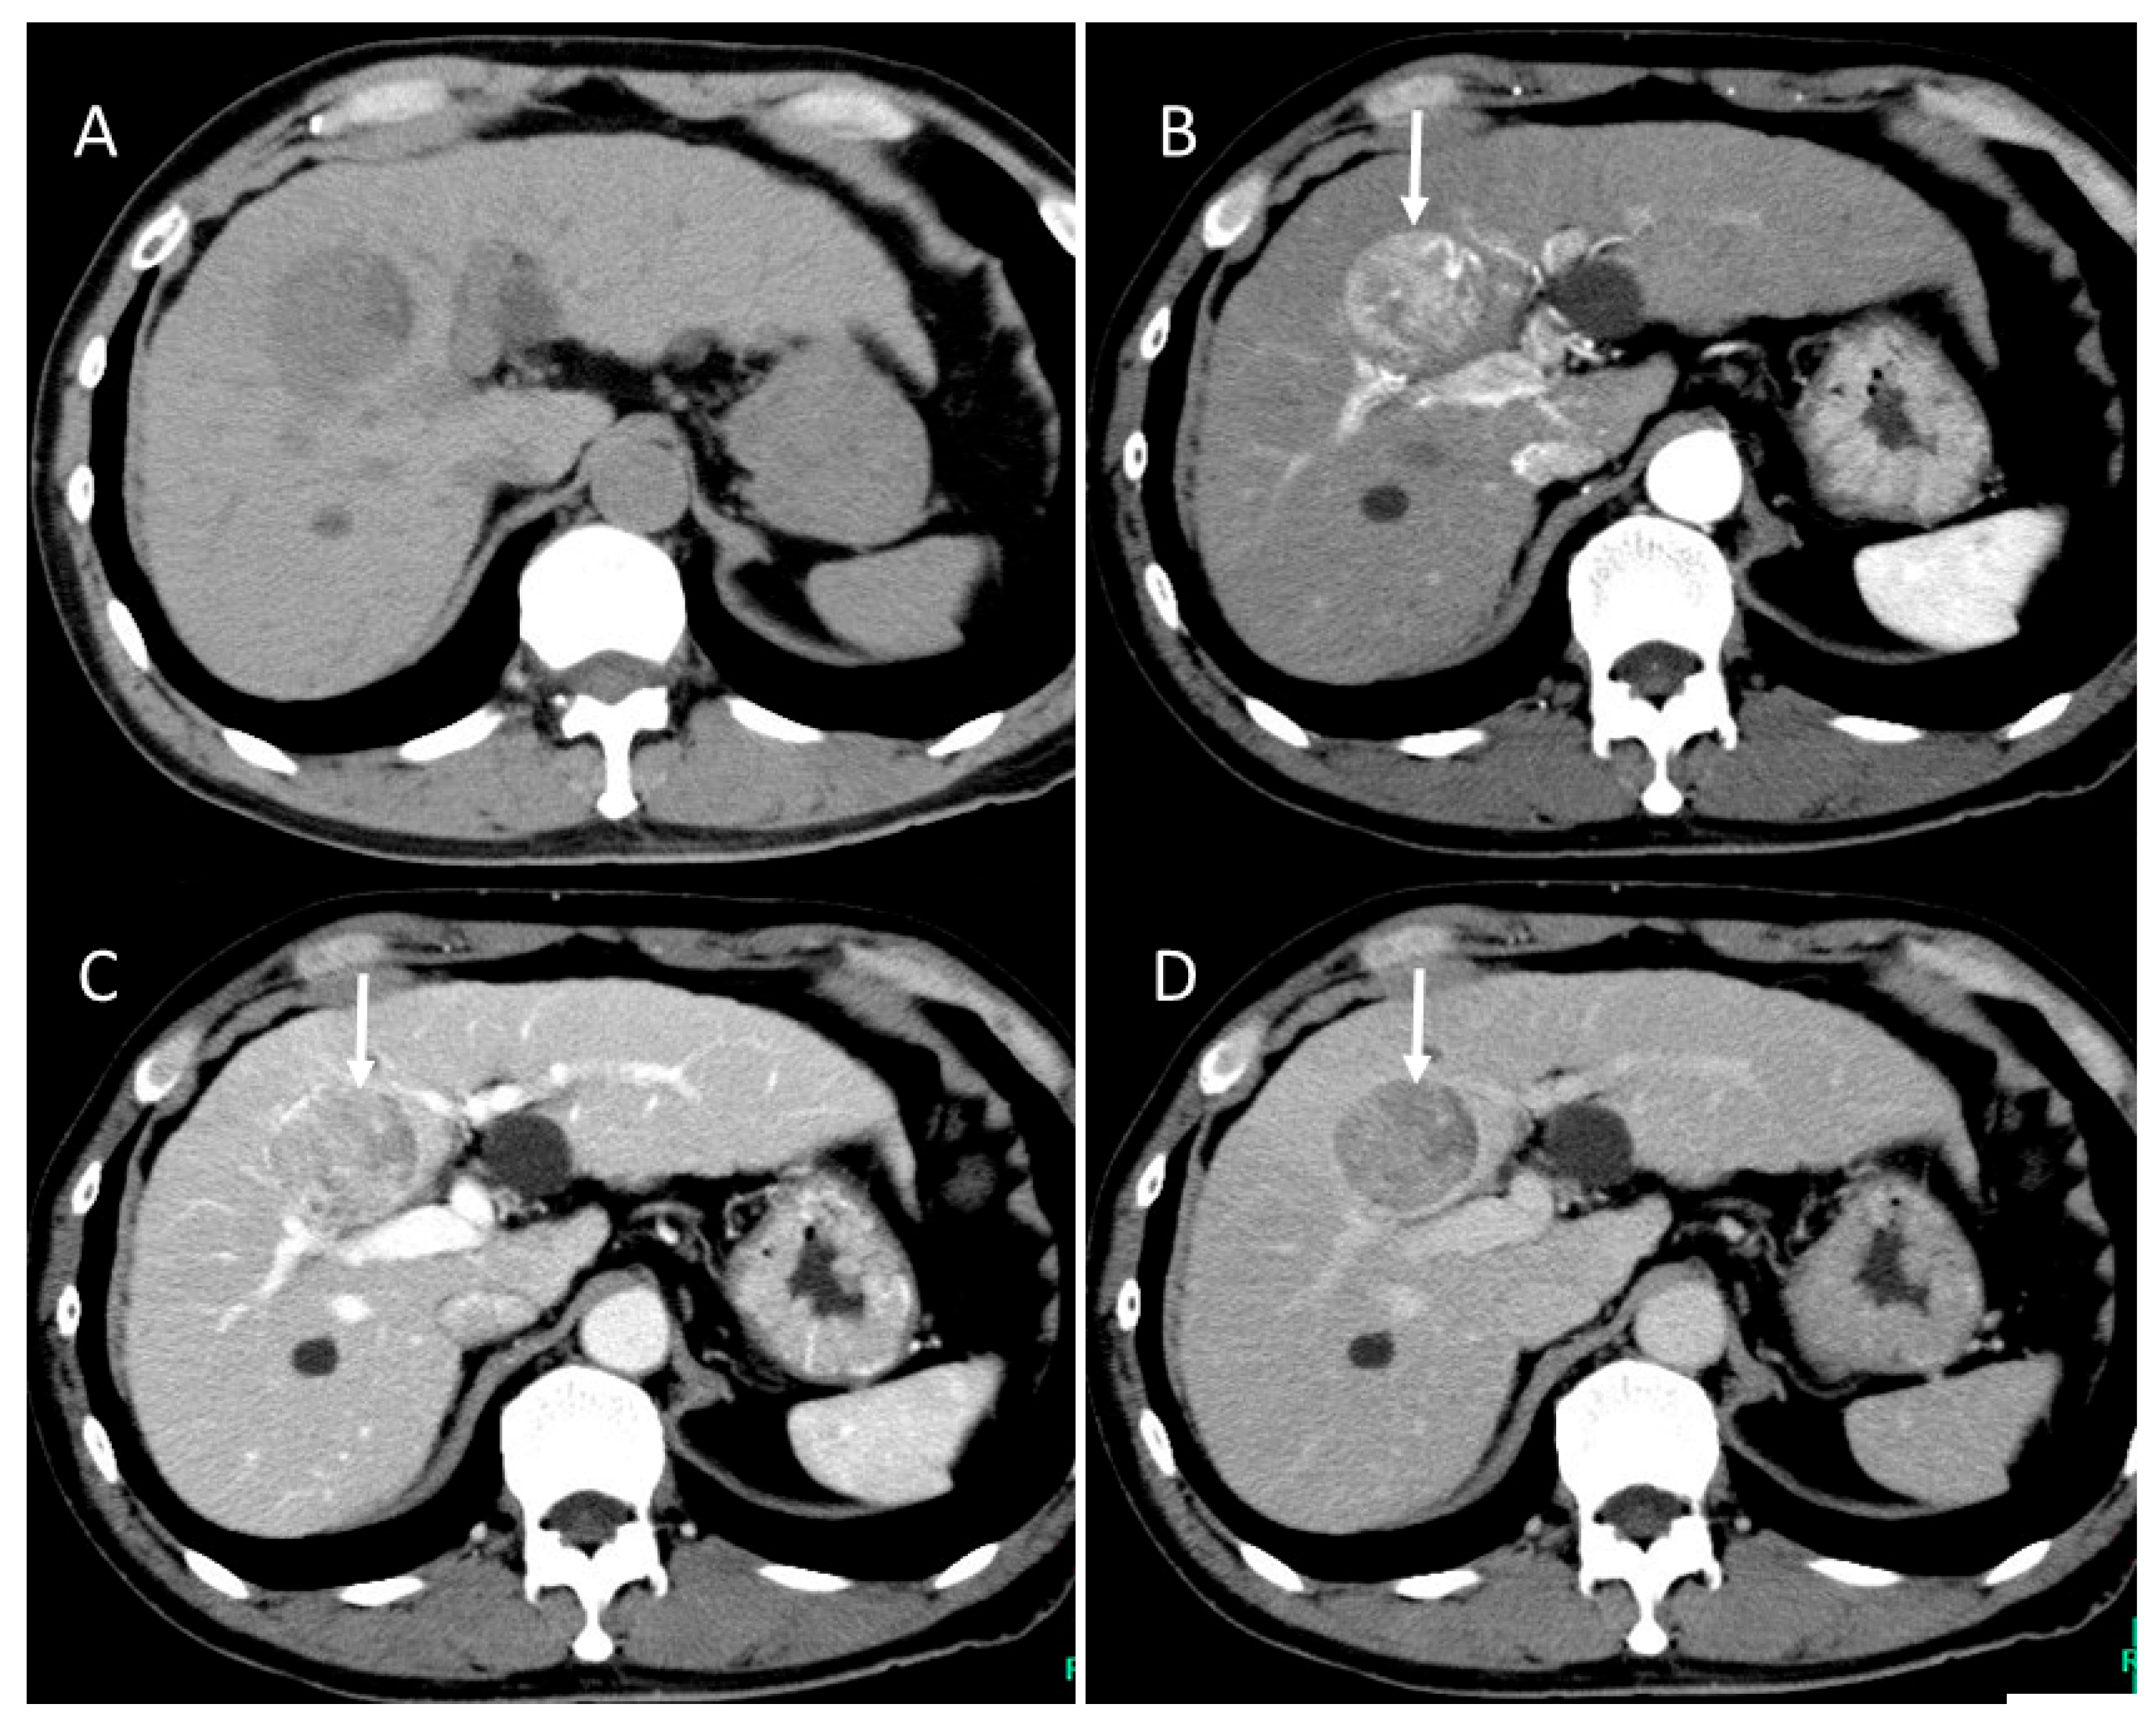

4.6. Fibrolamellar Hepatocellular Carcinoma (FL-HCC)